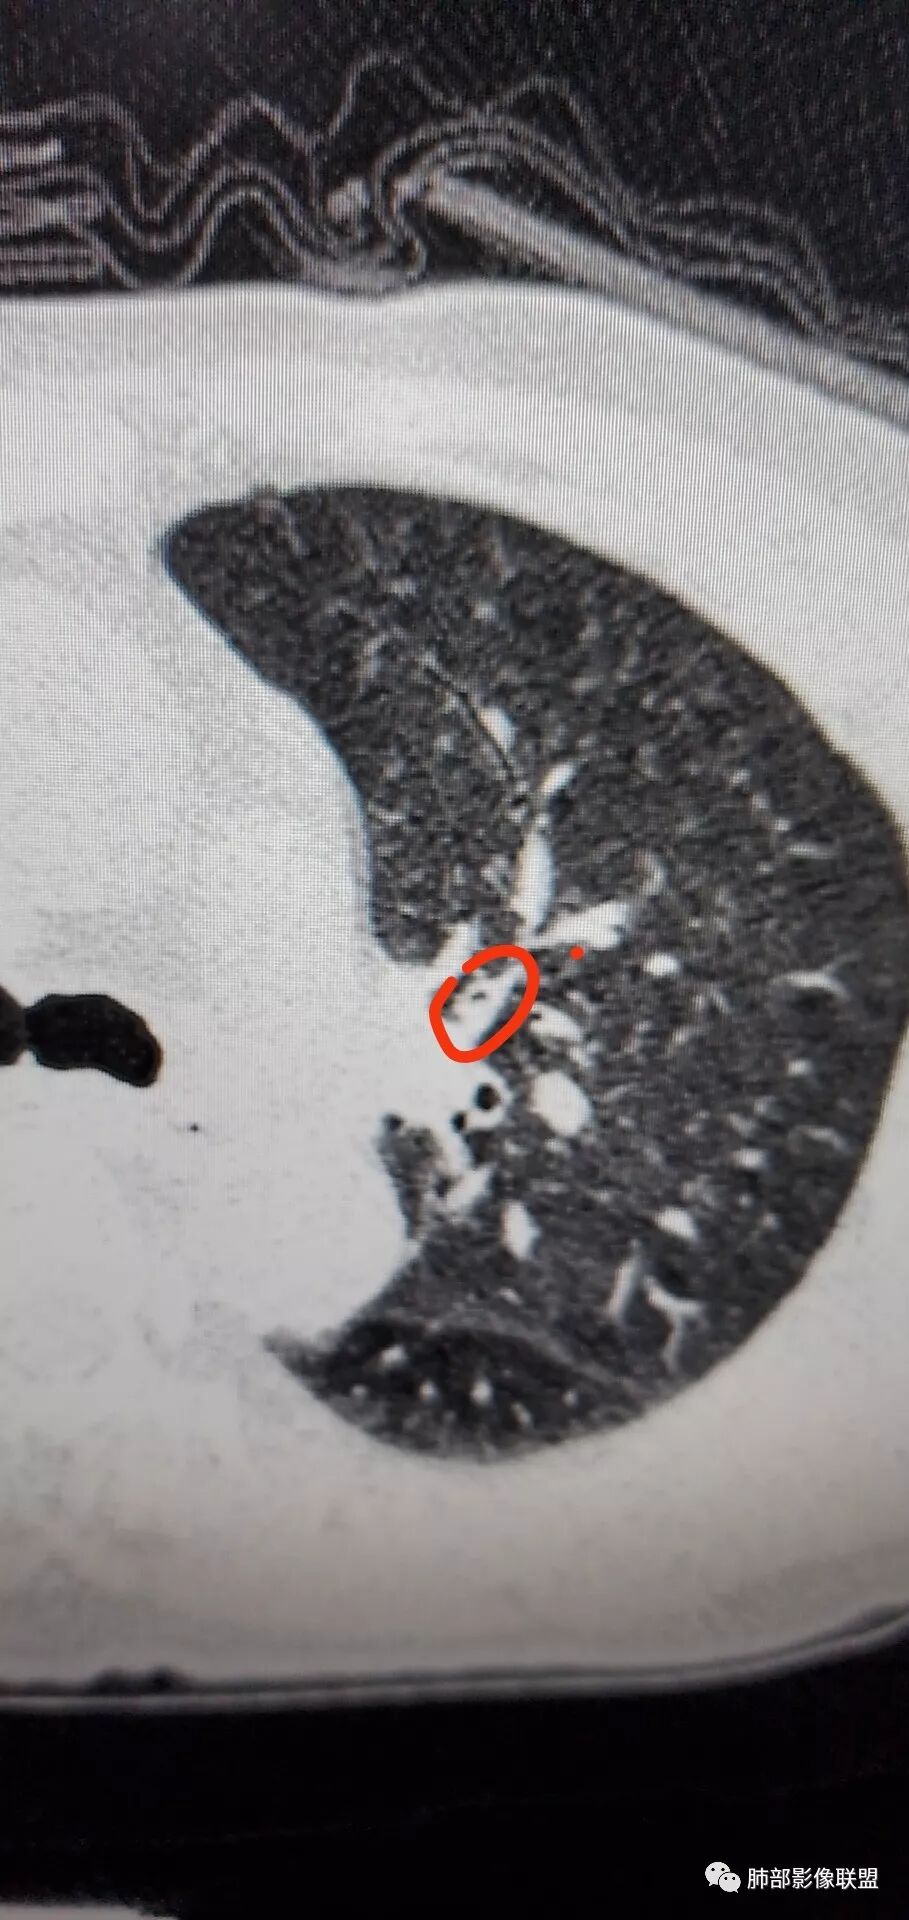

背段支气管有问题,局部有结节

左肺上叶病灶长轴与支气管走形一致,提示沿支气管分布病变,倾向于炎性,大家可能怀疑这个病例是来源于胸膜下为主的,胸膜下来源首先整体是来源于胸膜下,与胸膜下之间没有间隙,而这例与胸膜下有间隙。而且这个病变是沿支气管朝外蔓延的,而胸膜下来源的是朝内蔓延的,唯一给我们错觉的是靠近纵隔胸膜这个地方有问题。但是靠近纵隔胸膜这个位置实变不是靠近胸膜实变,它边缘收缩的,没有膨隆的迹象。我们看到里面支气管直达远端稍扩张,是以中央间质为主、小叶间隔朝外蔓延,有间质也有实质病变,走向是沿中央间质方向走的,我个人倾向炎性病变。    问题是右下叶病灶怎么解释?右隔上、右肺门各有一个结节。这个病人有急性咳嗽、胸痛的病史,还有糖尿病病史,周围渗出比较明显,应该警惕炎性病变,要警惕克雷伯杆菌、结核、金葡菌霉菌,因为糖尿病人经常好发这些病菌感染。那么右下叶病变怎么考虑?能不能一元论?    左肺病灶是一个急性渗出为主的病变,一个急性感染的迹象;右肺下叶背段结节,没有看到支气管,增强图支气管壁增厚,局部小结节,呈分叶状,支气管堵塞,没有粘液栓样指套样改变,但是里面有强化,我倾向于癌,其次待排结核。我还是倾向于癌的可能性,恶性可能性大一些,可惜我看不到支气管腔内。还考虑有没有淀粉样变性的问题,弥漫钙化灶最常见的一个是结核,另一个是淀粉样变性。叶段支气管壁有弥漫增厚的迹象。所以淀粉样变性跟结核都要考虑。

吴老师标记的这个支气管结节有点意思。其他的真是想不到鳞癌

右下肺病理没有报癌

背段入口在CT上也可以见到了

回头看尖段的分支和背段肯定是堵了,两处应该都是鳞癌,右肺基底段的就不知道了。

右下背还是考虑恶性可能

支气管镜下明显见到新生物了,病理取到表面粘膜。

鳞癌起源于支气管粘膜,是气道中最常见的恶性肿瘤,易造成支管壁增厚,并突入腔内形成结节,造成狭窄、阻塞或截断;早期鳞癌表现为沿支气管生长的梭形结节或局限性增厚,辖区内常出现阻塞性炎症,这样的病灶赢多平面重建并仔细观察支气管改变;如果有支气管壁偏心性增厚伴管腔狭窄或腔内结节形成,都要想到早期鳞癌的可能性,复查或内窥镜检查是必要的。

鳞癌好发于中老年人,与吸烟关系密切,如果发现不易吸收的,或同一部位反复无常局限性肺炎,我们应当仔细观察支气管壁的病变除外阻塞的可能;该病例右肺下叶背段及左肺上叶支气管有肿块及管壁的增厚,应当想到恶性可能。

1.右肺下叶支气管壁增厚,后壁为主,且显示壁外结节,未见异常强化。这样的结节和蔓延方式一般会高度怀疑气道来源的恶性肿瘤,如鳞癌、粘液表皮样癌、腺样囊性癌等。可惜没有相应病理学资料支持。